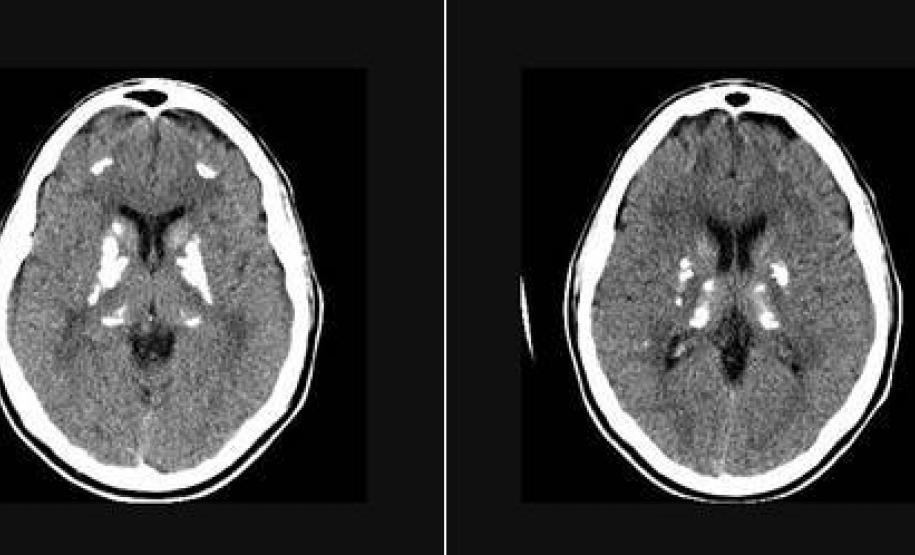

Ao saber sobre esse gene, Oliveira foi atrás de um modelo animal que permitisse detalhar o seu funcionamento. Encontrou Annika Keller, do Hospital Universitário Zurique, na Suíça. Ela estuda a barreira hematoencefálica usando camundongos em que o gene PDGF-B foi desligado, mas não tinha prestado atenção às calcificações cerebrais visíveis em tomografias. “Os camundongos simulam muito bem o que acontece em humanos”, afirma Oliveira. Para ele, encontrar esse modelo animal é importante porque permitirá testar drogas para combater os efeitos no cérebro da mutação recém-descoberta.